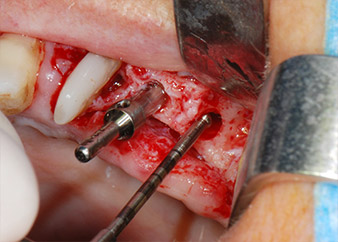

Implant beds were prepared at sites 25 and 26 with rotary instruments, used in a contra-angle handpiece with a 20 : 1 transmission ratio with an updated powerful implant motor (Implantmed, W&H) (Fig. 8).

The final preparation next to the sinus was again carried out with a piezoelectric instrument (Piezomed, insert S2).

Prior to implant placement, and following verification of an intact Schneiderian membrane (Fig. 9), the internal sinus floor was augmented at both implant sites by means of xenogeneic bone substitute material (Bio-Oss, Geistlich Biomaterials) (Fig. 10).

The implants (Restore, Keystone Dental, diameter 3,75 mm, length 8.0 mm) were placed with the implant motor

(Figs. 11 and 12).

Low speed insertion of implant 26

Fig. 11: Low speed insertion of implant 26 with a torque limitation of 35 Ncm.

ready for the cover screws

Fig. 12: Both implants in place and ready for the cover screws.